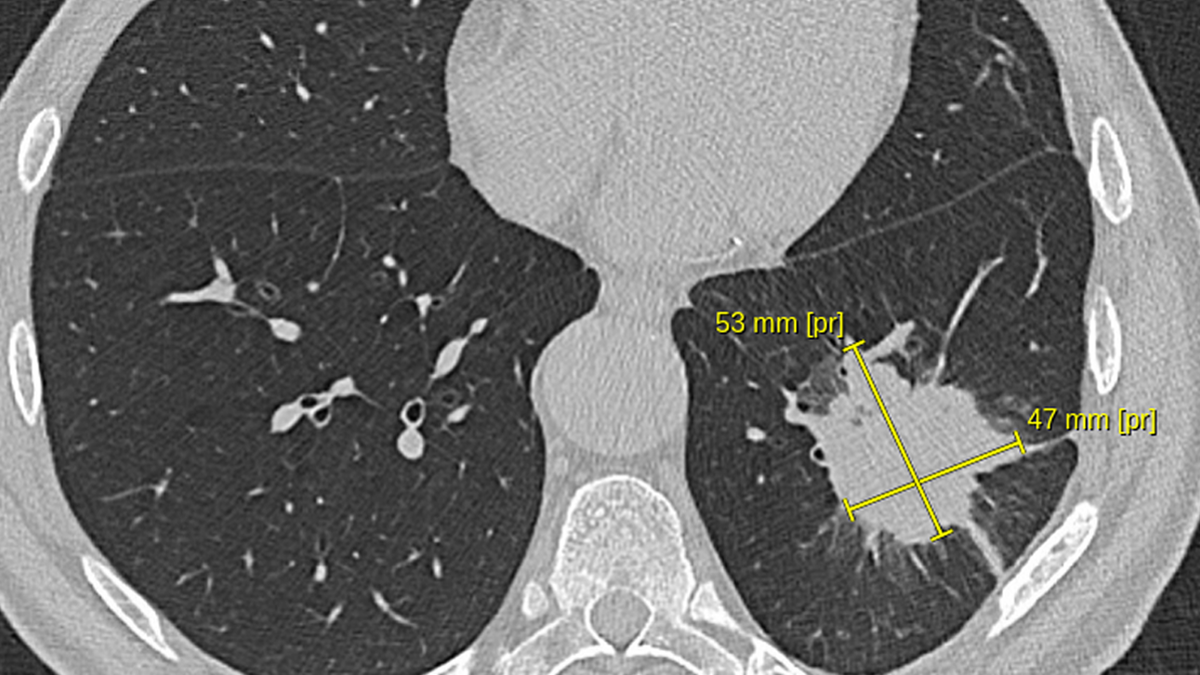

Мужчина 65 лет осенью 2024 года почувствовал себя плохо, стала подниматься температура до 38С, появился кашель с мокротой, иногда даже были прожилки крови. Обратился по месту жительства, был обследован терапевтом. По результатам анализов крови - воспаление, на КТ органов грудной клетки - следующая картина.

КТ органов грудной клетки при первичной диагностике

Из описания КТ ОГК:

Определяется наличие инфильтрата в S9 левого лёгкого, неправильной формы, размером до 53х47мм., с наличием периферической лучистости и тяжей к костальной и междолевой плевре.

Можно было бы сразу заподозрить опухолевый процесс, но врачей смутил следующий факт. Если пролистать снимки КТ чуть дальше, становится видна зона распада в данном инфильтрате, то есть признаки нагноения. На КТ это выглядело следующим образом.